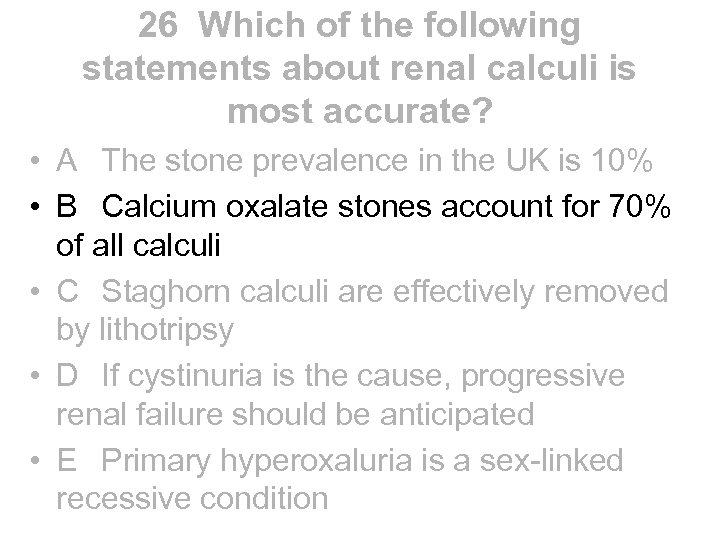

Lupus nephritis • Aetiology • - renal involvement occurs to some degree in most lupus patients, though drug induced lupus is said to spare the kidney • Presentation • - can vary from asymptomatic urine abnormalities to HT, NS, ARF, CRF • Diagnosis • - all patients with lupus and urine abnormalities should have biopsy to guide potentially toxic treatment regardless of serum creatinine. Histology can change from one type to another in the same patient. Six distinct patterns are recognised. Histology not similar to that of DN • 1 - normal • 2 a - mesangial deposits 2 b - mesangial hypercellularity • 3 - focal and segmental proliferative GN • 4 - diffuse proliferative (>50% glomeruli involved) causing RPGN • 5 - membranous • 6 - glomerulosclerosis

Lupus nephritis • Aetiology • - renal involvement occurs to some degree in most lupus patients, though drug induced lupus is said to spare the kidney • Presentation • - can vary from asymptomatic urine abnormalities to HT, NS, ARF, CRF • Diagnosis • - all patients with lupus and urine abnormalities should have biopsy to guide potentially toxic treatment regardless of serum creatinine. Histology can change from one type to another in the same patient. Six distinct patterns are recognised. Histology not similar to that of DN • 1 - normal • 2 a - mesangial deposits 2 b - mesangial hypercellularity • 3 - focal and segmental proliferative GN • 4 - diffuse proliferative (>50% glomeruli involved) causing RPGN • 5 - membranous • 6 - glomerulosclerosis

Lupus nephritis • • • Treatment 1 - no specific therapy 2 - steroids only 3 - steroids plus cytotoxic, may be cyclophosphamide 4 - steroids plus cytotoxic, usually cyclophosphamide 5 - controversial - likely to be steroids with azathioprine, mycophenolate or cyclosporin but not cyclophosphamide and not steroids alone 6 - controversial NB - cytotoxics indicated by histology and not simply by serum creatinine Outcome - glomerular sclerosis is most important predictor of ESRD - overall prognosis determined by presence or absence also of neuropsychiatric, cardiac and pulmonary disease

Lupus nephritis • • • Treatment 1 - no specific therapy 2 - steroids only 3 - steroids plus cytotoxic, may be cyclophosphamide 4 - steroids plus cytotoxic, usually cyclophosphamide 5 - controversial - likely to be steroids with azathioprine, mycophenolate or cyclosporin but not cyclophosphamide and not steroids alone 6 - controversial NB - cytotoxics indicated by histology and not simply by serum creatinine Outcome - glomerular sclerosis is most important predictor of ESRD - overall prognosis determined by presence or absence also of neuropsychiatric, cardiac and pulmonary disease